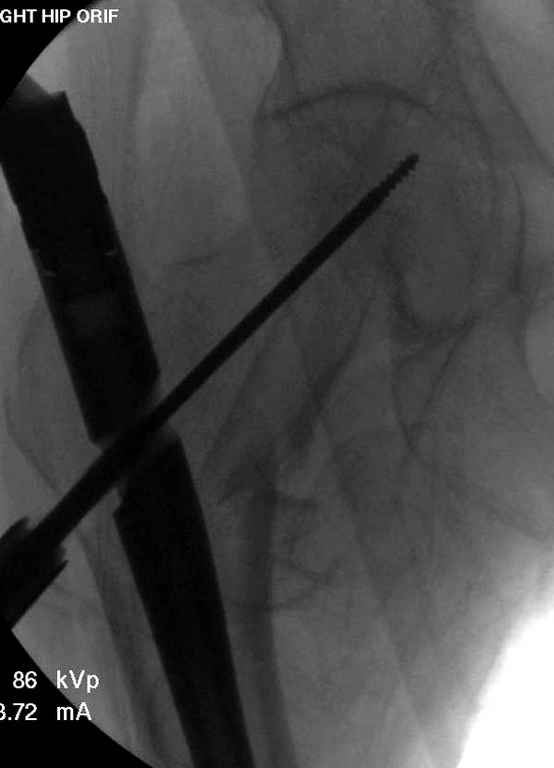

Хотелось бы увидеть снимки непосредственно после операции.

Перелом тут больше подвертельный. Нагрузка без торцевого упора на уровне перелома привела к телескопированию отломков на стержне. Ну и варус небольшой тоже свою лепту внес - если бы его не было, контактирующие латеральные стенки обоих отломков предотвратили бы укорочение, да и срослось бы за пару месяцев. А раз не срослось, упора отломков нет, более слабым местом оказались не нижние винты, а кость в головке и шейке. Так что надо было хотя бы удалить нижние винты до начала полной нагрузки.

На мой взгляд, причиной телескопирования явилось несоответствие диаметра гамма нэйл с диаметром канала подвертельного отдела бедра: обратите внимание на величину протрузии шеечного винта и величину медиализации дистального фрагмента - они одинаковы, смещение или телескопирование фрагментов происходило до того момента, пока гамма нэйл не упёрся в медиальный кортекс и образовалось пространство между латеральным

кортексом и латеральной поверхностью гвоздя.

Диаметр гаммы в диафизарной части ~11 мм. А диаметр канала, тем более у пожилых с остеопорозом, может быть мм 15. Даже рассверливать обычно не приходится, после формирования широкого канала в вертельной области можно сразу толкать гвоздь, он влетает, как карандаш в стакан. Так что соответствия диаметров не бывает никогда. Однако представленная ситуация случается далеко не каждый раз. Если гвоздь в центральном отломке входит чуть медиальнее верхушки вертела, и идет вдоль передне-латеральной стенки центрального отломка, то все будет хорошо.

В приложении похожий пример, к счастью, пациентка появилась не после, а "за полчаса" до протрузии. Пересинтезировали с исправлением ошибок.